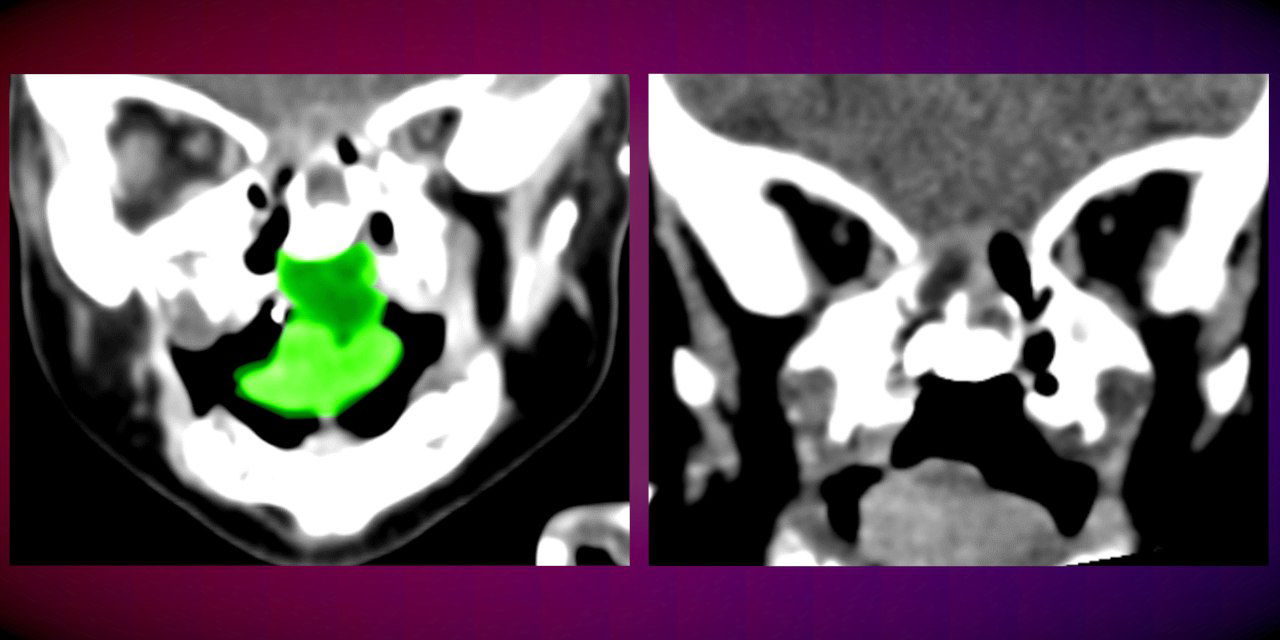

י' נולדה עם מום מסכן חיים – גידול נדיר ומסיבי שהתפתח בחלל הפה והלוע שלה בעודה ברחם אמה ותפס חלק ניכר מהאזור. בשל גדלו של הגידול, התינוקת סבלה מחסימה של נתיב האוויר ואי יכולת להיות מוזנת באופן טבעי, דרך הפה.

במהלך הניתוח, שארך מספר שעות, ביצע צוות רב תחומי כריתה של הגידול החוסם בשלמותו, תוך שמירה על רקמות בריאות שנמצאות מסביבו. ההליך הכירורגי העדין, אותו ביצעו ד"ר עומרי אמודי, וד"ר טל קפושה מהמחלקה לכירורגיה פה ולסתות בניהולו של פרופ' עדי רחמיאל, וכן, ד"ר וסילה ראצ'ה מרדים בכיר, הסתיים בהצלחה ובסופו הועברה התינוקת להמשך התאוששות ביחידה לטיפול נמרץ ילדים, שם שהתה מספר ימים.

ד"ר קפושה מציין כי בהמשך יתכן ויהיה צורך בטיפולים נוספים משלימים, ובעקבות כריתת הגידול יתכן שהפעוטה תזדקק לטיפול שיקומי וכירורגיה משחזרת של החך להשלמת הטיפול בה.